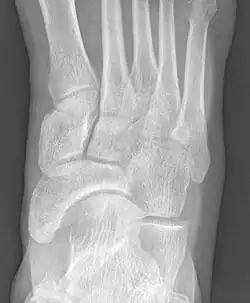

To diagnose accessory navicular syndrome, the foot and ankle surgeon will ask about symptoms and examine the foot, looking for skin irritation or swelling. The doctor may press on the bony prominence to assess the area for discomfort. Foot structure, muscle strength, joint motion and the way the patient walks may also be evaluated. X-rays are usually ordered to confirm the diagnosis. If there is ongoing pain or inflammation, an MRI or other advanced imaging tests may be used to further evaluate the condition.[5]

Radiological images